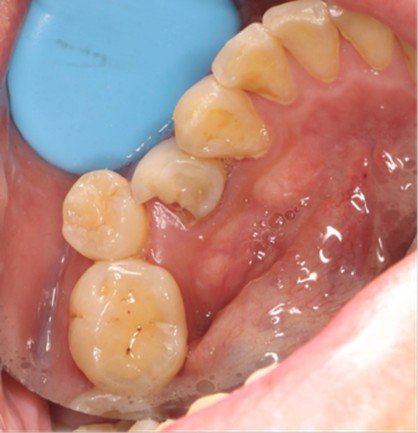

May 4, 2025: Extraction of the affected tooth.

Immediate implant placement (first-stage surgery) was performed right after tooth extraction.